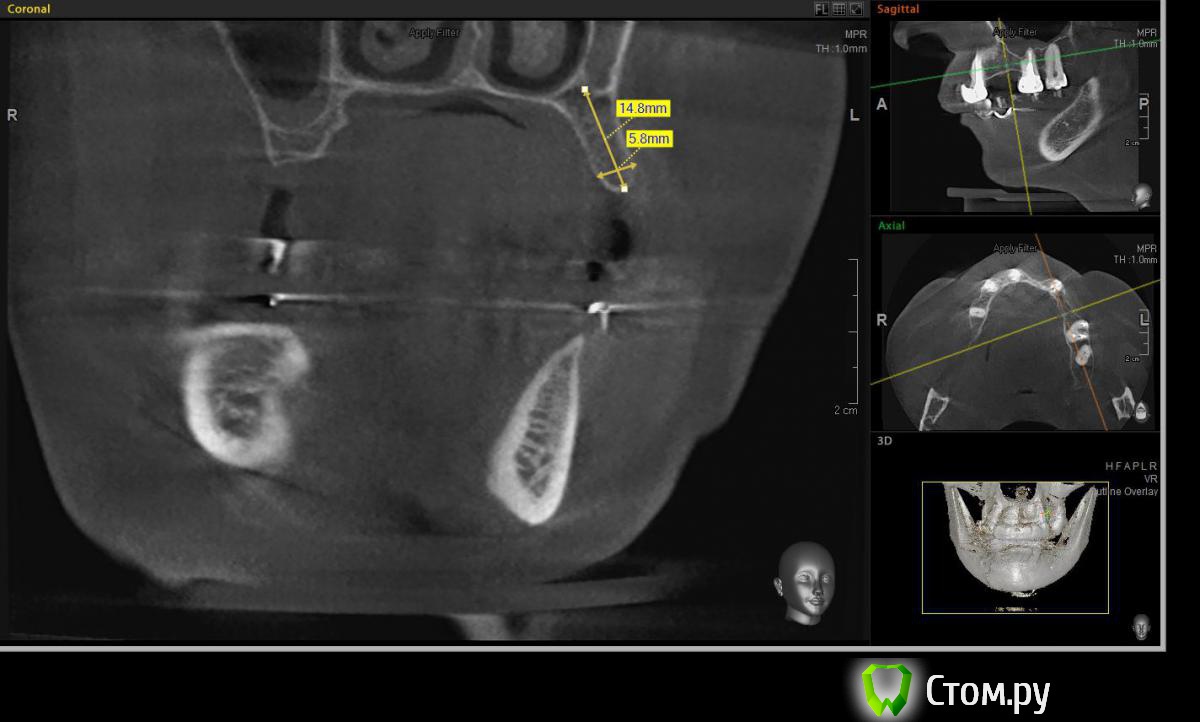

Евгений Ходыкин Опубликовано 23 июля, 2014 Поделиться Опубликовано 23 июля, 2014 Решили с пациенткой пока начать с в.ч. В планах имплантация в область отсутствующих 1.6, 1.4, 1.2, 2.1, 2.2, 2.4, 2.5. С 1.6 самому более менее все понятно, мануальных навыков хватит) Прошу помощи коллег относительно остальных областей. Фронт особливо печален... Забегая наперед скажу, что блоки еще не делал. Ауто точно пока брать не планирую, ибо нет даже теоретических навыков. Хочу начать все-таки с аллоблоков. У кого какие будут мнения, заранее спасибо) Ссылка на комментарий

Евгений Ходыкин Опубликовано 24 июля, 2014 Автор Поделиться Опубликовано 24 июля, 2014 В области 2.4 выраженная нёбная резорбция. Крепить мембрану туда, или все-равно наращивать вестибулярно?? Ссылка на комментарий